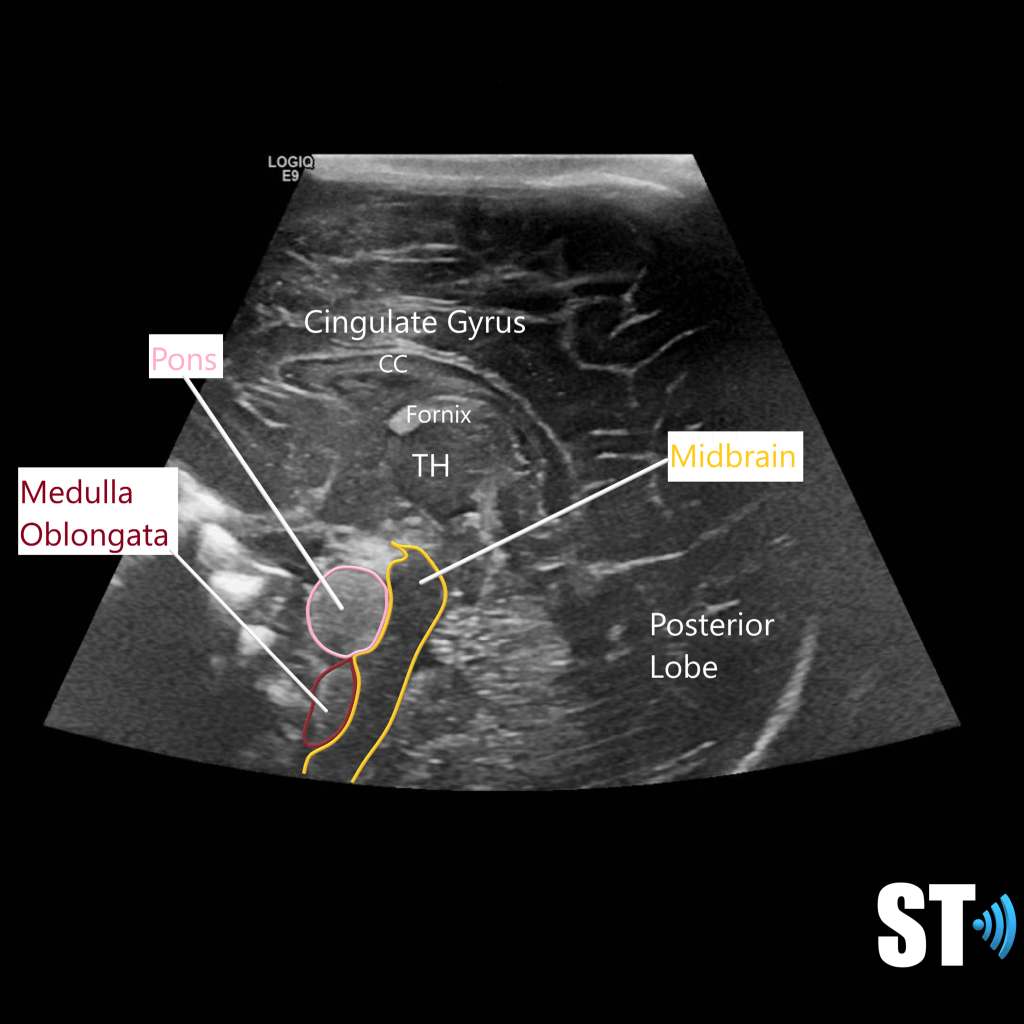

A robust knowledge of neuroanatomy is required for the execution and interpretation of these exams. The brain is divided into 3 main areas the cerebrum, cerebellum and brain stem. It has many convolutions called sulci and gyri that increase the surface area.

The Cerebrum is the most cephalad portion and consists of 4 lobes: frontal, parietal, temporal and occipital lobes. The separation of these lobes is by way of fissures, which are large grooves. Important ones that pertain to sonographic imaging are the sylvian Fissures, cingulate gyrus and the interhemispheric fissure, which divides the brain into right and left hemispheres.

These hemispheres are connected by the corpus callosum (CC), a large bundle of nerve fibers that allow the hemispheres to communicate. There is a fluid filled structure right below that CC called the septum pellucidum. This structure is an important marker in the fetal brain to rule out structural anomalies.

The ventricular system is a series of chamber deep within the brain that collect and allow the flow of cerebrospinal fluid. The main components are the paired lateral, third and fourth ventricles.